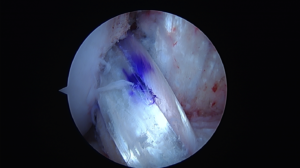

A newer way of treating ACL tears is ACL repair. This takes advantage of modern sports medicine arthroscopic techniques that allow the torn ACL to be re-anchored back in place.